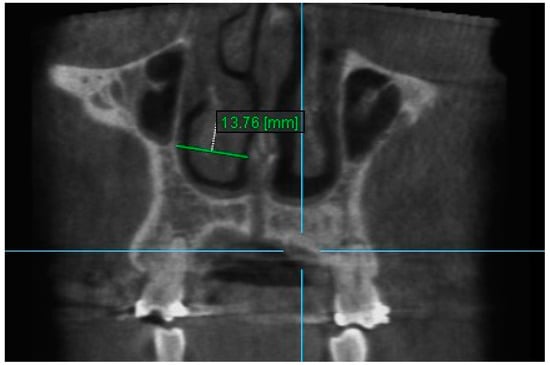

1. Nasal Width 1: The maximum lateral interior width of nasal cavity on coronal slice through the center of the mesial buccal root of the first permanent molar (Figure 3).

Figure 3.

Nasal Width 1.

2. Nasal Width 2: The maximum lateral interior width of nasal cavity on coronal slice through the center of the root of the second premolar (Figure 4).

Figure 4.

Nasal Width 2.